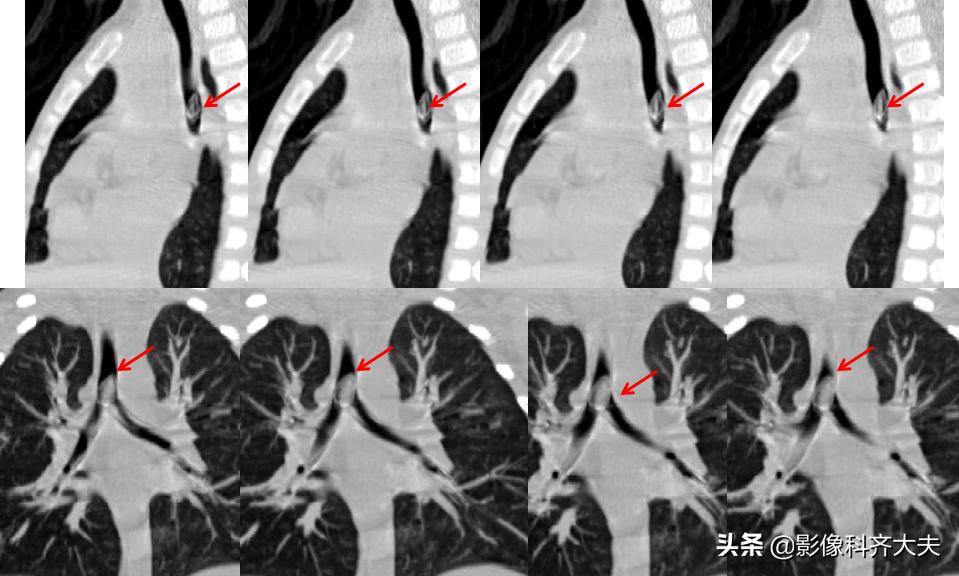

病例1、病史:患儿,女,一岁半,咳喘两周,病前有“开心果”吸入史。

图为轴位及冠状位重建图显示异物:红色箭头为异物的位置,冠状位显示尤为清晰。